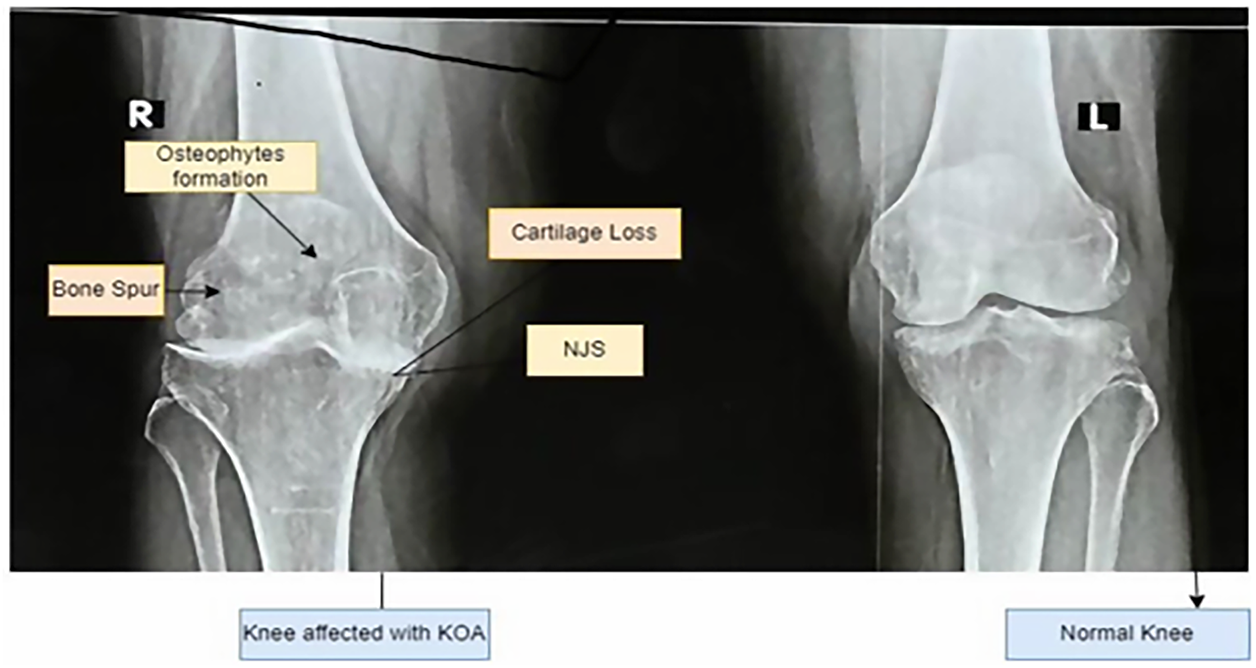

Clinical diagnosis of KO continues to rely heavily on the interpretation of plain radiographic images. Radiologists assess structural indicators such as tibiofemoral joint space width, osteophyte formation, subchondral sclerosis, and surface deformities to estimate disease severity [4]. These features form the basis of the Kellgren Lawrence grading system, which categorizes osteoarthritis into discrete stages ranging from normal to severe [5]. While widely used in clinical practice, this grading process requires substantial expertise and remains susceptible to inter-observer and intra-observer variability, particularly in early and moderate stages where radiographic differences are subtle [6]. In addition, the increasing volume of medical imaging data places a growing burden on radiology workflows, further motivating the need for automated and reliable diagnostic support systems. Fig. 1 illustrates how joint space narrowing is used as a central indicator of cartilage loss. Healthy knees show a clear and preserved joint space, while moderate and severe conditions exhibit progressive narrowing that reflects structural degeneration and loss of load-bearing capacity. Fig. 2 provides an enlarged view of a healthy and an osteoarthritic knee, highlighting pathological changes such as cartilage erosion, the formation of osteophytes, and the thickening of subchondral bone. These observable characteristics help clinicians identify the stage of knee osteoarthritis, but their interpretation requires considerable expertise.

Figure 1: Knee with Osteoarthritis and without Osteoarthritis.

Figure 2: Enlarged view of a normal knee and Knee osteoarthritis affected.